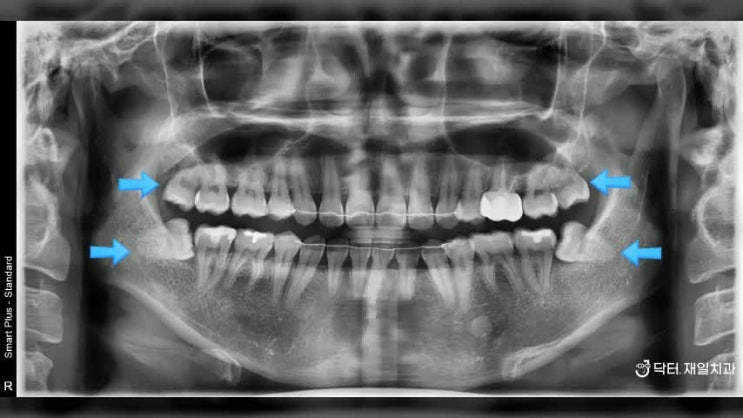

사랑니발치 매복된 경우에도 수면마취치료로 잠자면서 편안하게 ! 8호선 별내 다산사랑니 치과 찾는분도 오시는 저희 치과

사랑니발치 매복된 경우에도 수면마취치료로 잠자면서 편안하게 ! 8호선 별내 다산사랑니 치과 찾는분도 오...